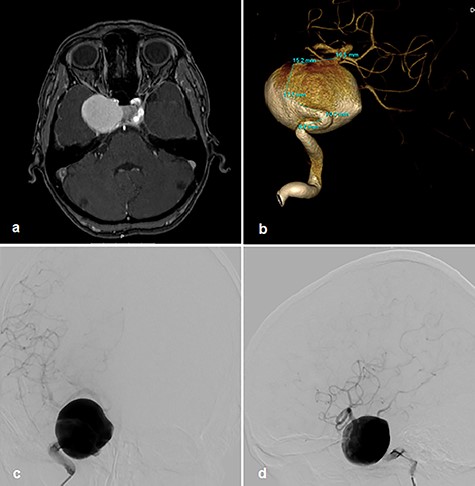

A 56-year-old woman without significant prior medical history presented with ptosis on the right side as a sign of external oculomotor palsy. Magnetic resonance (MR) imaging investigation confirmed a large mass lesion of 30 mm in diameter parasellar on the right side without perifocal edema. In MR angiography, we suspected a giant aneurysm of cavernous internal carotid artery (ICA). In the digital subtraction angiography (DSA), a giant cavernous part ICA aneurysm with wide contact to parent vessel was confirmed (Fig. 1a–d). We decided on treatment by vessel reconstruction using Pipeline™ flow diverter stent. This treatment failed after incorrect unfolding of the sheet stent in the curved part of the vessel just proximal to aneurysm neck. Several attempts to unfold the stent failed. For this reason, the intervention had to be terminated without success.

Right cavernous ICA Aneurysm on MR TOF angiography (a); DSA 3D angiogram (b); p–a projection angiogram (c); lateral angiogram (d).